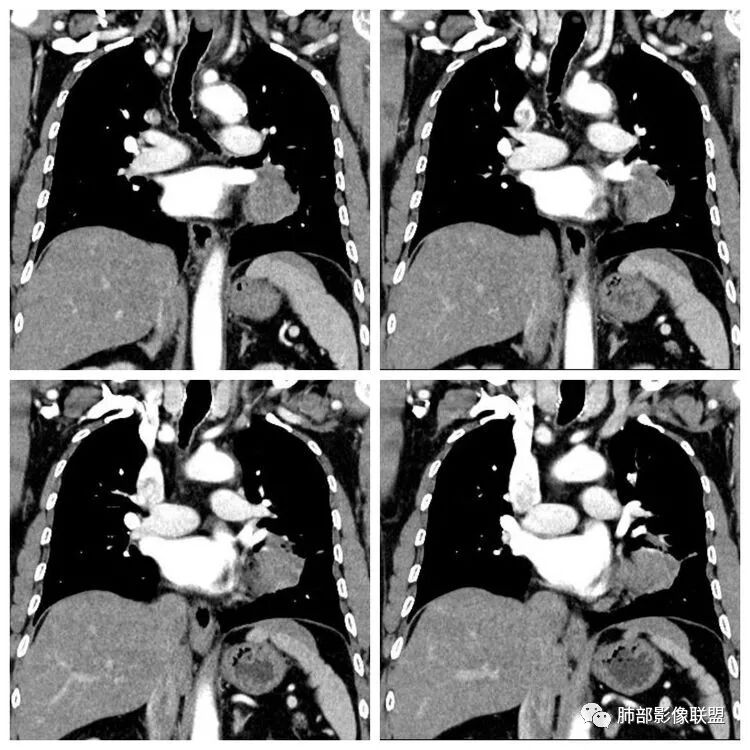

平扫 动脉期 静脉期  40HU、48HU、57HU

患者老年男性,“左肺占位”收入住院。查CEA轻度升高。胸部CT:左肺肺门占位并左肺下叶阻塞性,远端肺组织膨胀不全,增强可见轻度强化,内似见低密度灶。双肺多发类圆形结节,以左肺上叶尖后段为大,内可见部分钙化,边缘光滑、清楚。综合考虑恶性病变,鳞癌并转移可能大,鉴别腺癌、结核。

胸CT:左下叶内前基底段肿块,支气管堵塞,强化弱,延迟强化,两肺多处结节,右上肺门淋巴结大。常规考虑:肺癌可能 ,肺内小结节,转移?鉴别:错构瘤,TB等。

1.定位:左肺块影同时累及下舌段及下叶内基底段且相互延续。病灶跨叶,或存在叶裂发育异常,或者说就是病灶的肺门蔓延。

2.病灶前上部分与舌段支气管相关且形成阻塞。

4.增强扫描左肺门区块影轻度强化,强化程度轻于舌段周围不张肺组织。

5.双肺门及纵隔未见明确增大淋巴结。

6.分析:男性患者,左肺门区块状影,支气管阻塞,强化不显著,未见淋巴结肿大,更多见于肺鳞癌。难以解释的是下肺病灶的生长方式。

沿肺门或是叶裂缺损孤立发生且蔓延,转移性腺癌似乎可以解释,但占据较大支气管腔就属罕见了。